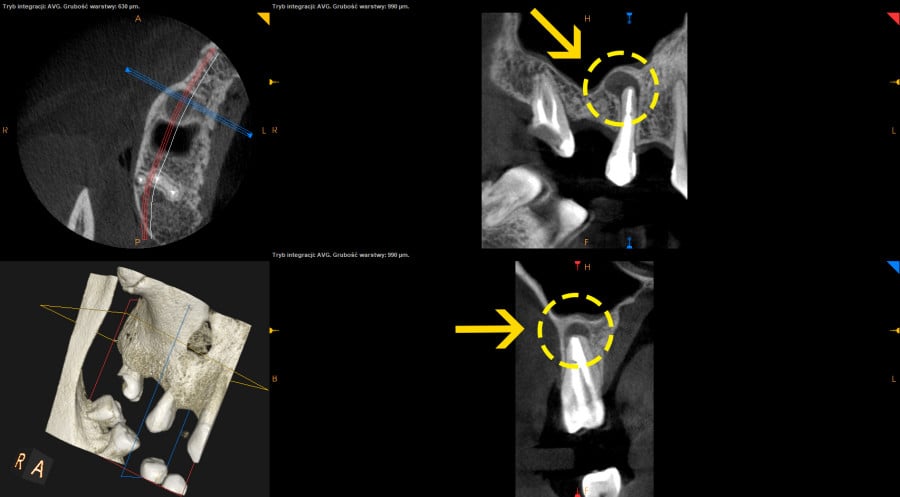

• Wykonanie nowoczesnej diagnostyki pozwoliło na znacznie szybszą ocenę gojenia w stosunku do prześwietleń takich jak ortopantomogram lub radiowizjografia i skróciło okres obserwacji gojenia.

• Pacjent juz po 4 miesiąch od leczenia endodontycznego mógł wrócic do protetyka celem wykonania mostu porcelanowego.